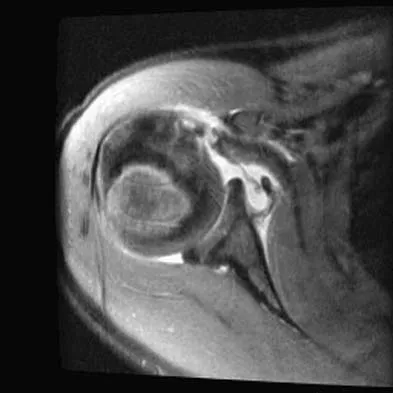

A 25-year-old carpenter falls on his outstretched arm. What physical finding best correlates with the lesion seen on the MRI scan shown in Figure 3?

The MRI scan shows disruption of the subscapularis muscle. Subscapularis rupture is associated with weakness in internal rotation as shown with a positive lift-off test as described by Gerber and Krushell. The belly press test also has been shown to be a useful clinical test for this problem. Weakness in external rotation and abduction is more consistent with supraspinatus and infraspinatus tears. Deltoid atrophy is associated with an axillary nerve injury. Loss of biceps contour is associated with rupture of the long head of the biceps. Gerber C, Krushell RJ: Isolated rupture of the tendon of the subscapularis muscle: Clinical features in 16 cases. J Bone Joint Surg Br 1991;73:389-394.